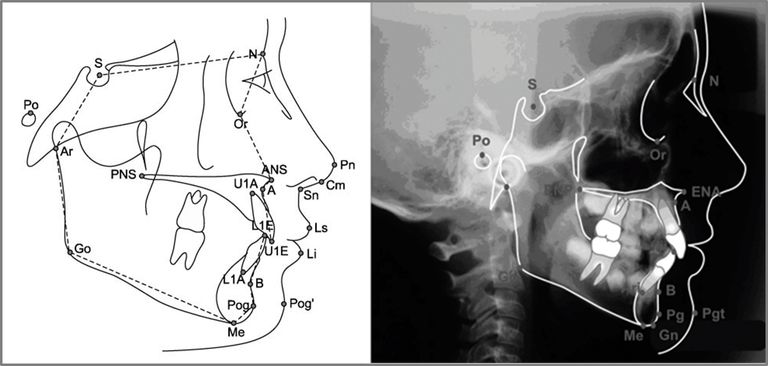

1、『Influence of Mouth Breathing on the Dentofacial Growth of Children: ACephalometric Study』

他们搜集了共50位6~12岁的小朋友

并分为三组

鼻子呼吸(10位)

嘴巴呼吸(同时因腺体肿大造成鼻子阻塞约60%)(20位)

嘴巴呼吸(鼻子通畅)(20位)

并用头影测量

他们比较他们在头颅和长相上的差距

发现口呼吸的小朋友,明显牙齿较暴(U1-L1 angle)

同时在自然放松的情况下嘴巴皆会不自觉地开开(Interlabial gap)

2、『The Effect of Mouth Breathing Versus Nasal Breathing on Dentofacial and Craniofacial Development in Orthodontic Patients』

总共收集了116位正在做牙齿矫正的小朋友

年龄范围在10~14岁之间

依照口呼吸与鼻呼吸分别分为二组

1.口呼吸组(n=55)-平均年龄12.49岁

2.鼻子呼吸组(n=61)-平均年龄12.55岁

头影测量上的差距也十分明显

他们发现口呼吸的人有较高比

根据研究发现:呼吸和鼻呼吸影响长相——长期的口呼吸会导致脸型几个改变

暴牙2.脸型变长3.下颔后收4.放松时嘴巴不自觉打开